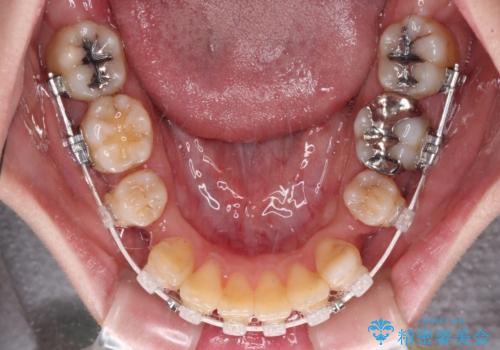

- 矯正装置

- 審美装置

口元の突出感はありませんが、前歯の重なりが著しいため、目立ちにくい表側のワイヤー装置にて、上下左右の第一小臼歯4本を抜歯して矯正治療を行うこととしました。